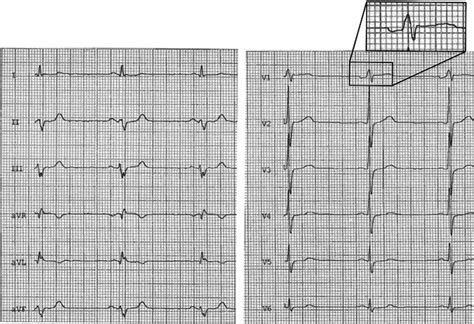

Identifying a posterior infarct ECG involves recognizing specific changes in the ECG leads that reflect the posterior wall of the heart. The key diagnostic criteria include:

• ST-segment depression in leads V1 and V2, which are the right precordial leads.

• Tall R waves in leads V1 and V2, often accompanied by ST-segment depression.

• Reciprocal changes in the anterior leads, which may include ST-segment elevation in leads V7, V8, and V9 (if available).

These changes are often subtle and can be easily missed if not carefully examined. The table below summarizes the key ECG findings in a posterior infarct ECG.

ECG Lead Key Finding

V1 and V2 ST-segment depression and tall R waves

V7, V8, V9 ST-segment elevation (if available)

It is essential to note that the standard 12-lead ECG may not always capture the posterior leads (V7, V8, V9). In such cases, additional posterior leads may be required to confirm the diagnosis.